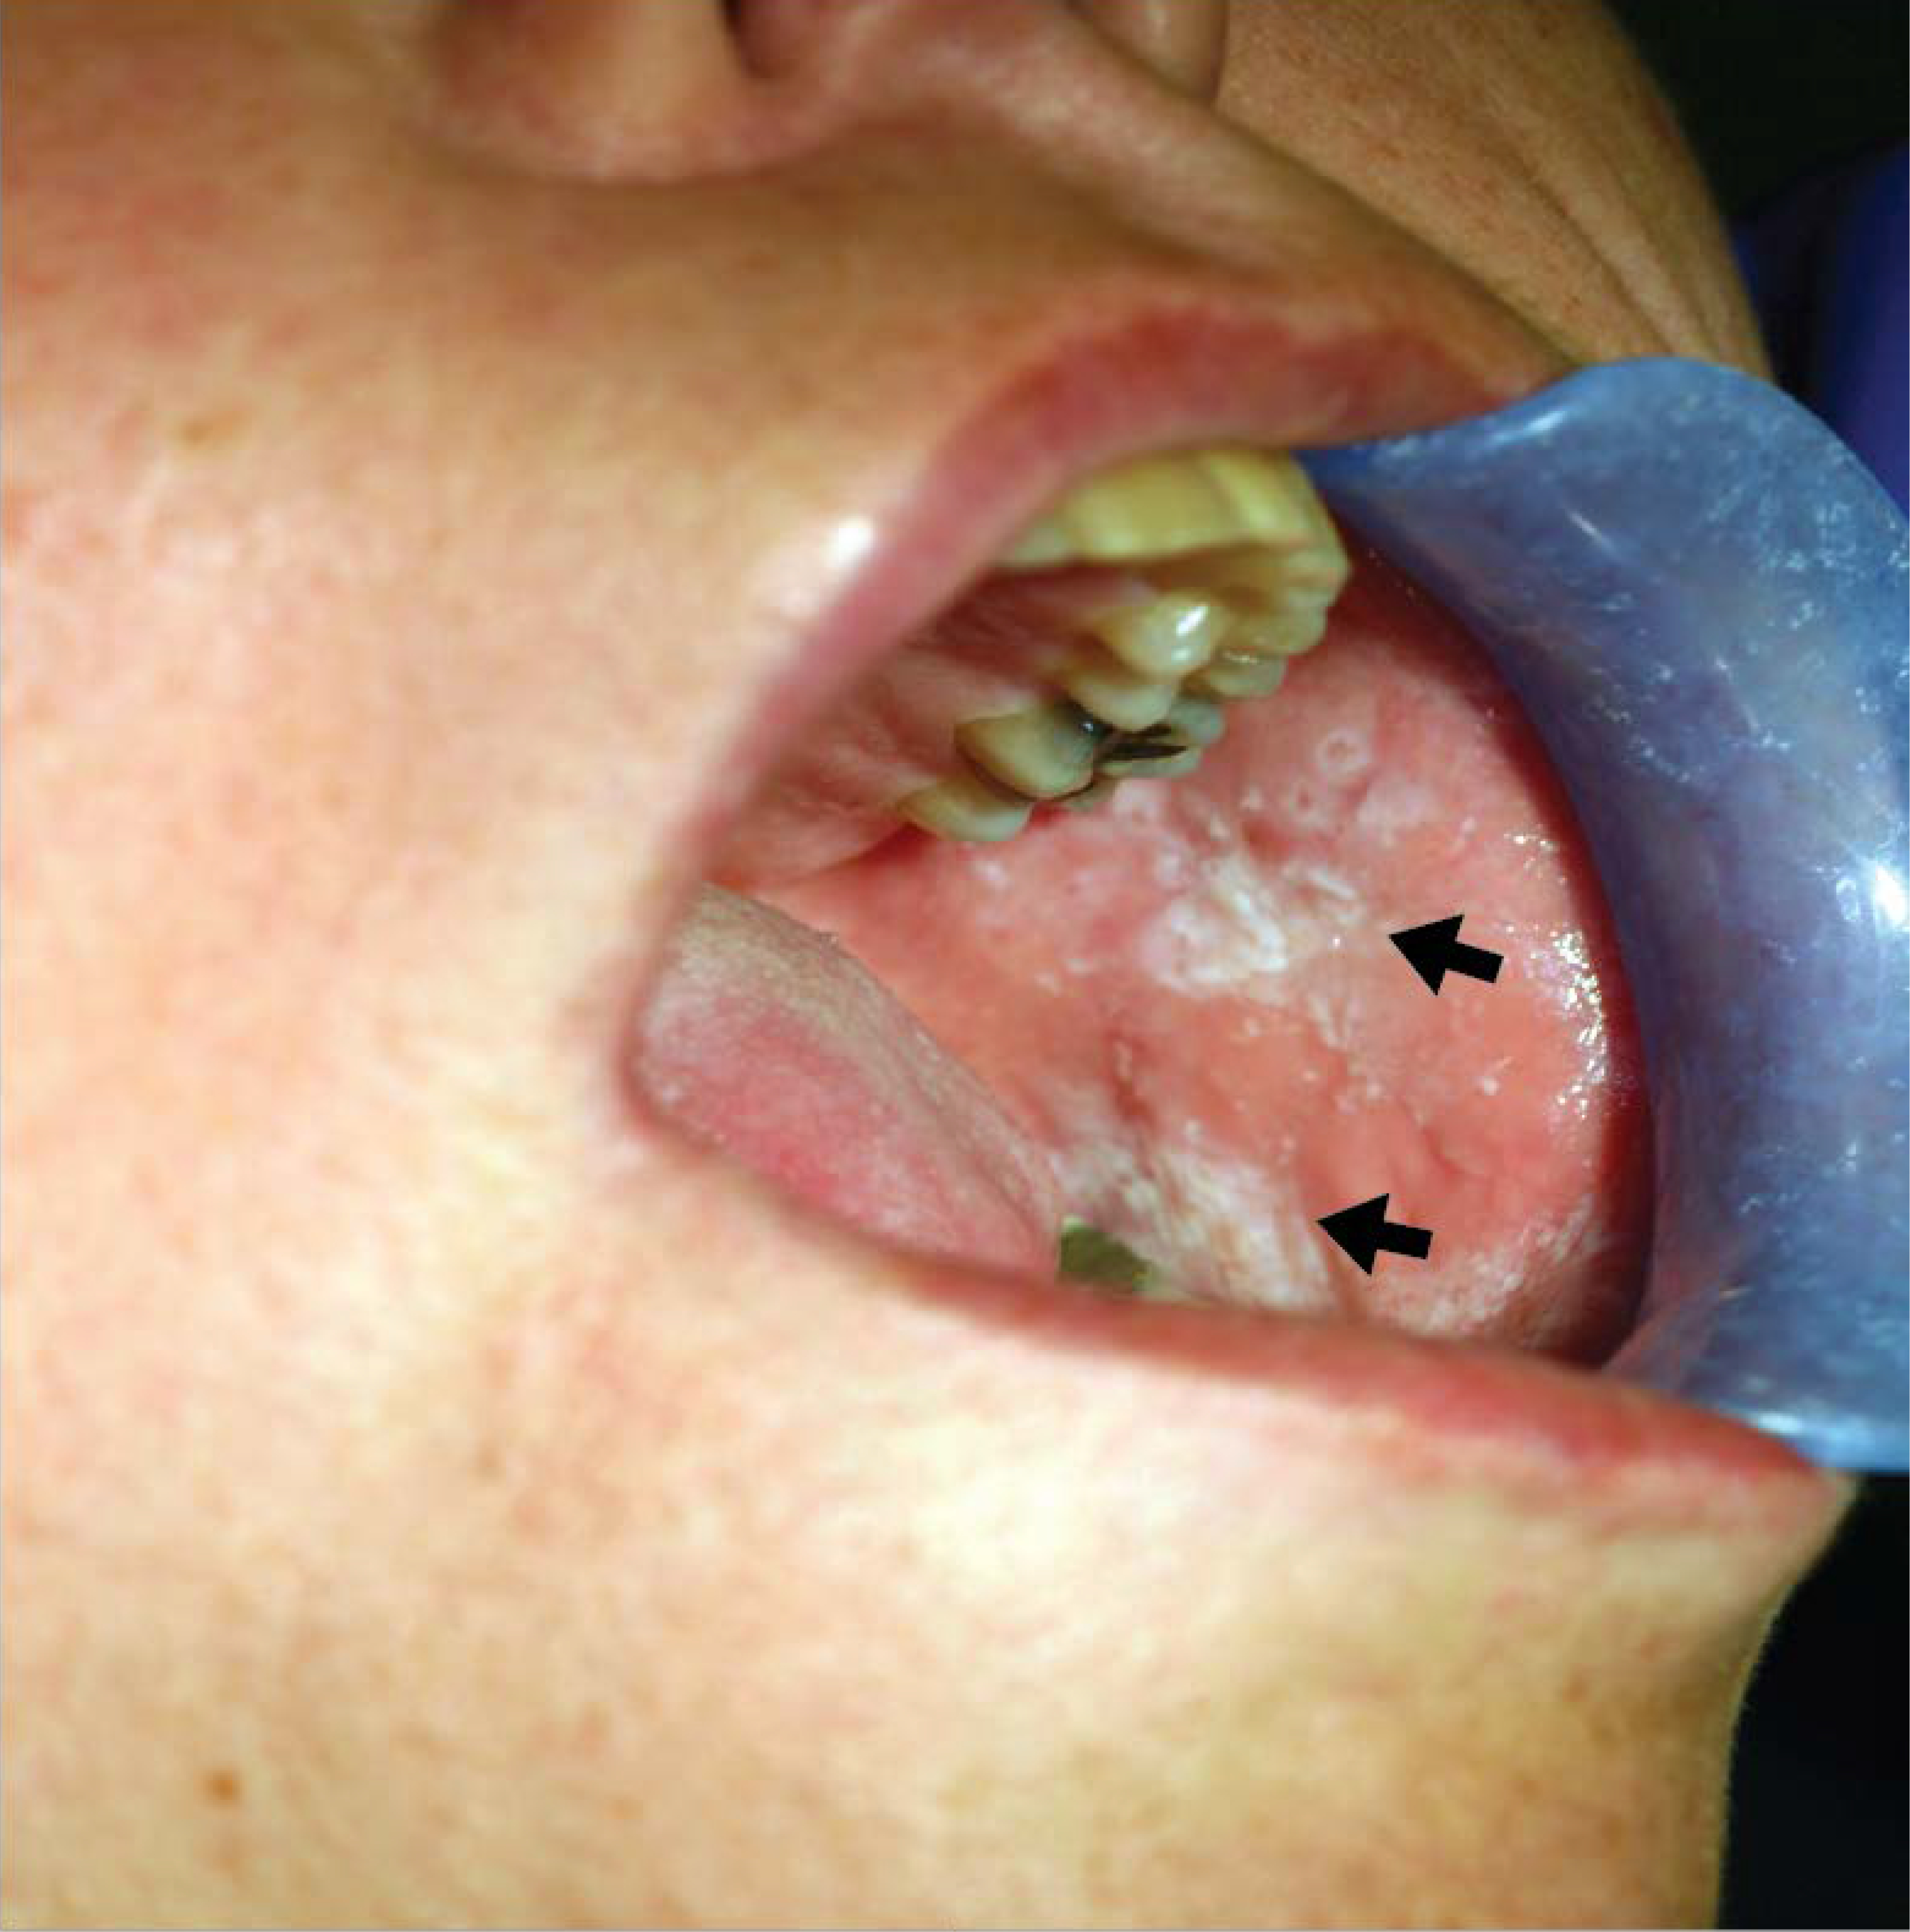

Drug-drug interactions are an obvious major concern for dental healthcare professionals because we identified 1595 drug entries in the Lexicomp online drug database for dentistry that were associated with local anesthetic precautions. This is highly significant considering that local anesthetics are the most commonly used drugs in dentistry. Although not a top category listed in this study, benzodiazepines commonly used to treat anxiety and insomnia may cause a patient to develop tolerance to anesthesia prompting the clinician to give higher doses of local anesthetics for dental procedures 34. Also, tricyclic antidepressants tend to potentiate the vasoconstrictive action of epinephrine, a common component of local anesthetics cartridges used in dentistry. It is vital to also consider that oral ulceration, lichenoid eruptions (Figure 5), hyperpigmentation, mucosal swelling and taste alterations are common oral adverse drug reactions, but these rarely cause significant alterations in dental treatment 2. Of the 46 clinical trials identified (Table 5), 40 studies focused mainly on analgesics, so there is still paucity of data from hypothesis driven studies that assessed direct relationships between different drugs and dental treatment complications. Therefore, more original studies to address the knowledge gap in this area are still warranted. There are some weaknesses of the current study. The methodology used in this systematic review focused mainly on dental treatment complications that are recurrently listed in ‘Lexicomp Online for Dentistry’ drug database which obviously introduced an inherent bias to search terms selected. However, databases that document specific cardiovascular (e.g. hypertension), metabolic (e.g. diabetes mellitus), hematological (e.g. anemia, bleeding) and central nervous system (e.g. cognition) related issues will be more clinically-relevant to dental practitioner treating medically complex patients related issues

Figure 5.

Oral lichenoid drug reaction. This patient developed lichenoid drug reaction of oral mucosa (black arrows) to a non-steroidal anti-inflammatory drug.